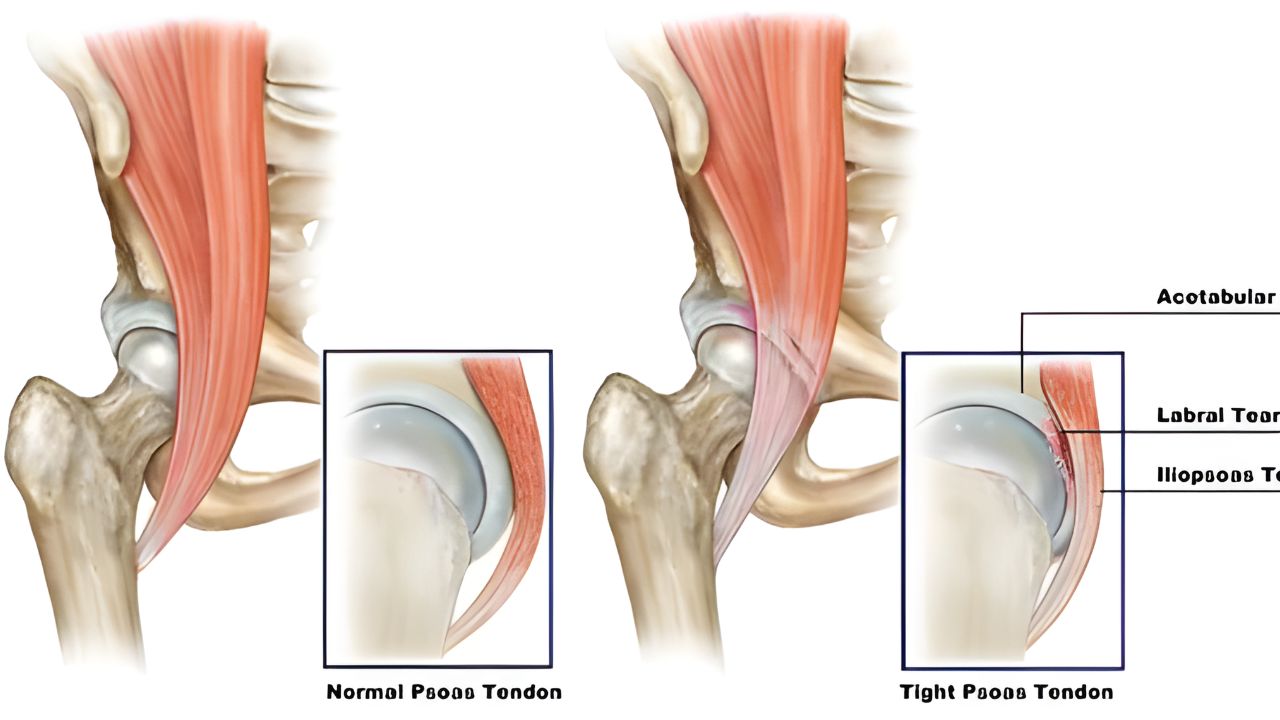

Principais causas do ressalto no quadril O encurtamento muscular e o desequilíbrio biomecânico são as causas mais comuns. A tensão excessiva na banda iliotibial ou no tendão do iliopsoas faz com que essas estruturas “saltem” sobre os ossos durante o movimento. Além disso, alterações intra-articulares, como lesões no labrum ou corpos livres, também podem gerar travamentos e estalos profundos, limitando a função articular.

Sintomas que indicam a síndrome O sinal mais evidente é o som de “clique” ou a sensação de salto ao mover a perna. Quando há inflamação associada, surge dor na lateral do quadril (ressalto externo) ou na virilha (ressalto interno). Pode haver sensação de que o quadril está “saindo do lugar”, fraqueza muscular e dificuldade para realizar atividades esportivas que exigem grande amplitude de movimento.